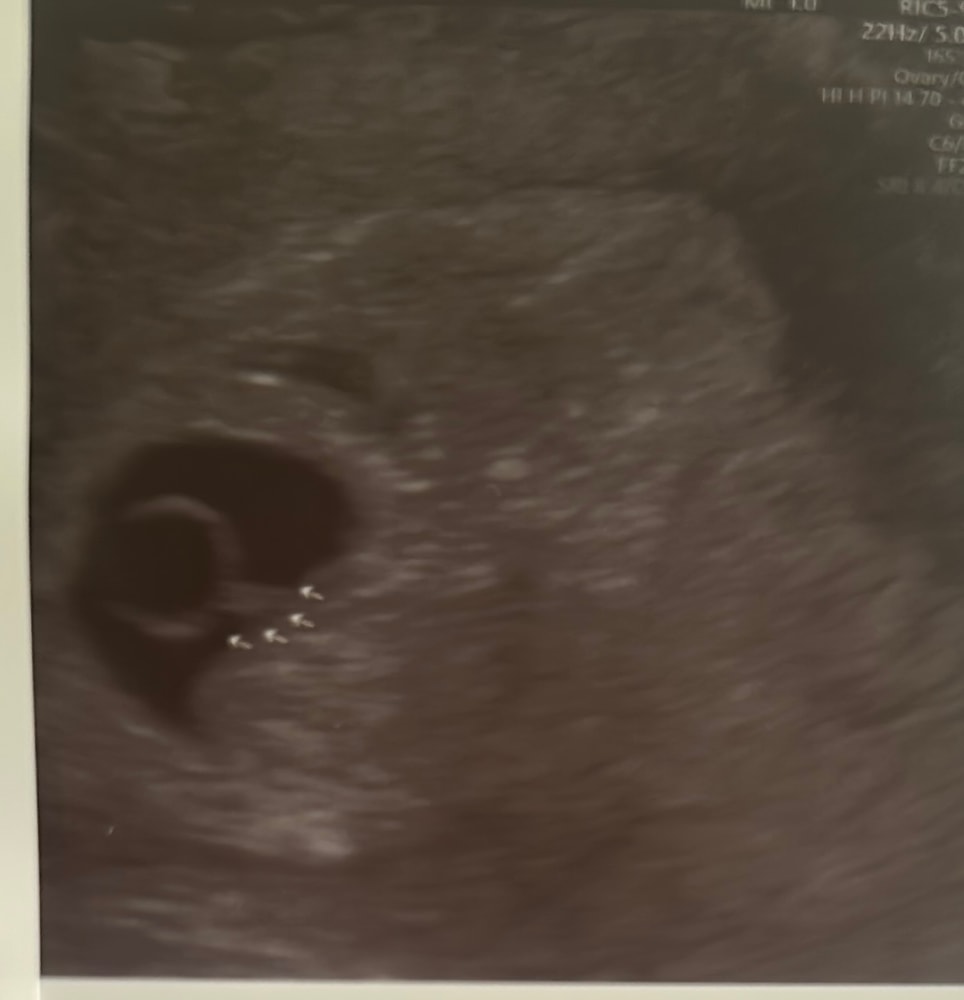

Марина, вот такое кольцо с бриллиантиком сказали бриллиантик это эмбрион Изображение

Alina, могли ошибиться,слишком рано для эмбриона,5 недель всего,девочки на 1 УЗИ идут на 21 дпп и то у 95% нет эмбриона,и ещё у 5% он только-только появляется и размером 1 мм,а у вас 19 дпп и уже 2 мм,сомнительно,видела здесь на 19 дпп тоже нашли ктр 1,7,но это был не ктр,перепутали с чем-то